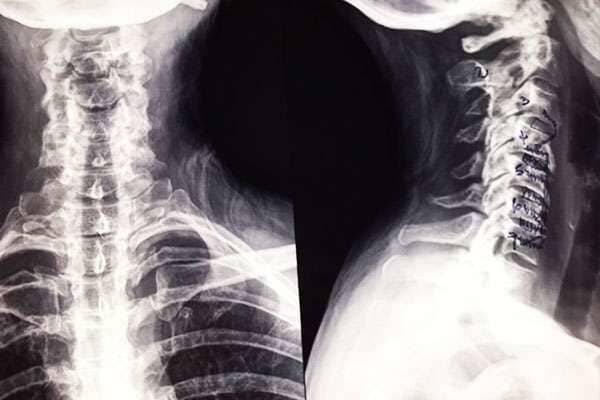

El

Dr. Hugo Octavio Arredondo García, médico ortopedista, traumatólogo y cirujano de columna vertebral, cuenta con estudios de Posgrado en Cirugía Ortopédica infantil, así como constantes cursos de actualización en todo el mundo para mantenerse a la vanguardia en cuanto a técnicas y procedimientos de

ortopedia, traumatología y cirugía de columna vertebral, ofreciendo sus servicios en la ciudad de

Chihuahua, Chihuahua.